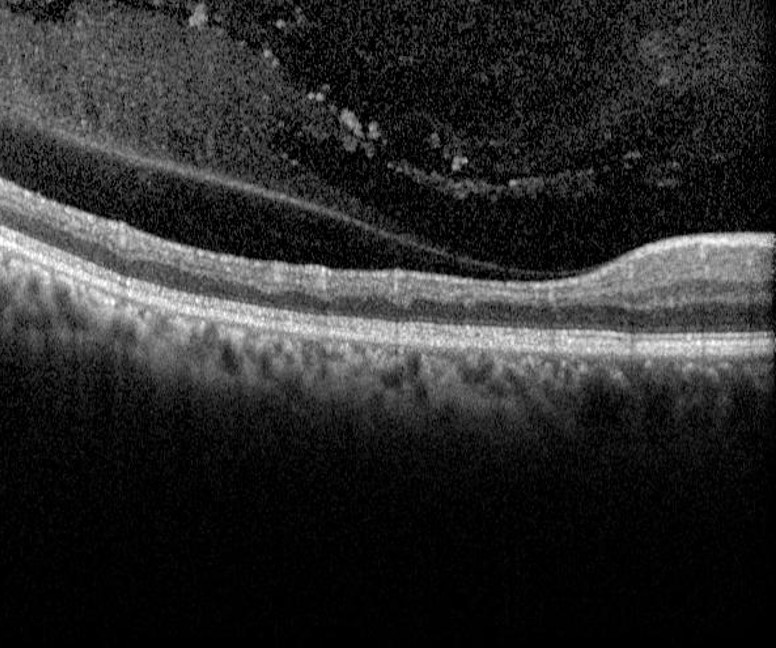

Over time, a chronic arterial occlusion results in atrophy and loss of the inner retinal layers which can be detected with OCT imaging. Neovascularisation is very rare in all forms of retinal arterial occlusion.